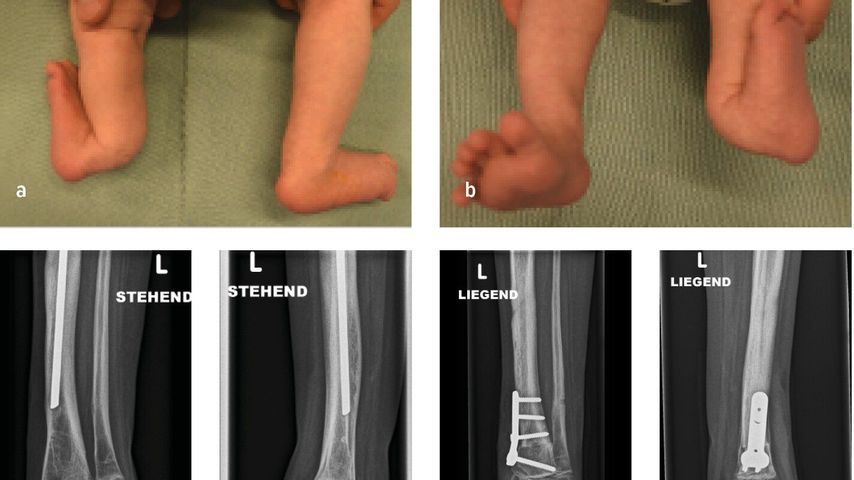

Kongenitale Deformitäten des Unterschenkels gehören zu den seltenen, aber medizinisch bedeutenden und operativ herausfordernden Diagnosen der Kinderorthopädie. Eine differenzierte ...

Die Herstellung eines symmetrischen Gangbilds sowie die Verbesserung der kinetischen und kinematischen Gangparameter im Gangzyklus stellen das Hauptaugenmerk in der Behandlung von ...